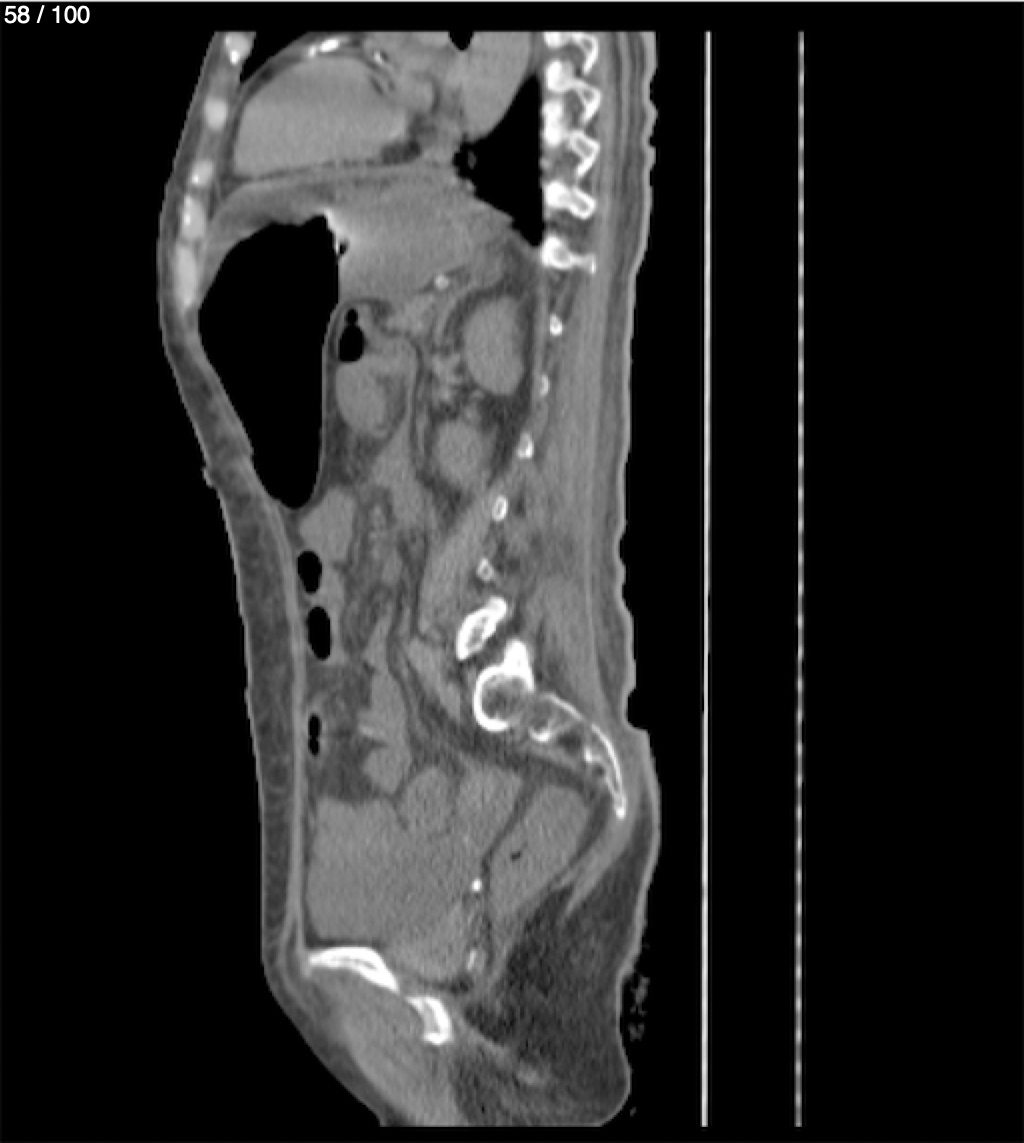

Hilda Geronimo Mendez 60A - T.C Abdomen Simple